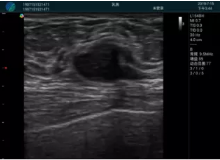

可視化甲狀腺穿刺引導(dǎo)

甲狀腺囊性結(jié)節(jié),囊壁鈣化,透聲好

甲狀腺囊性占位

2001年美國健康護(hù)理研究和質(zhì)量監(jiān)督局(AHRQ)批準(zhǔn)了一項(xiàng)關(guān)于提高患者安全性的報告,建議:在頸內(nèi)靜脈中心置管術(shù)時使用超聲引導(dǎo)。此后超聲引導(dǎo)穿刺被用于幾乎所有的急診穿刺操作,尤其是血管穿刺。

便攜超聲在急診穿刺中的應(yīng)用:

* 提高了穿刺成功率

* 減少了穿刺損傷及并發(fā)癥

* 縮短了操作時間

* 減輕了患者痛苦